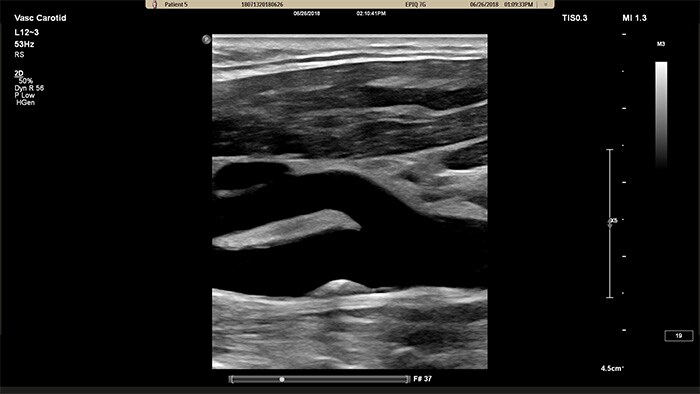

XL14-3 xMATRIXトランスジューサは、縦断面および横断面を同時にリアルタイムで描出して血管検査の標準アプローチを超える、xPlaneイメージングを提供します。xPlaneイメージングの主なメリットとして、トランスジューサを回転することなく直交断面を収集できる点が挙げられます。トラックボールのシンプルな動きで、完全な解剖学的評価を提供し、検査時間を短縮できます。